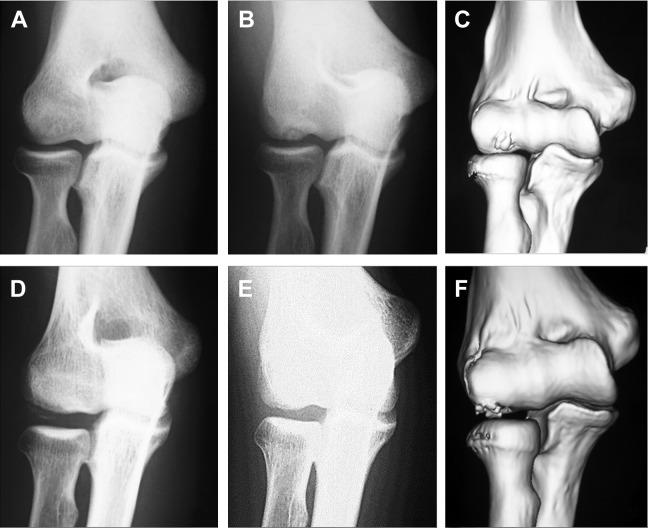

Subjects consisted of 95 baseball players (95 elbows) and 21 gymnasts (24 elbows) with a mean age of 13.7 years (range, 11-18 years). To localize the lesion, inclination of the affected area in the humeral capitellum against the humeral axis was investigated using sagittal computed tomography images of the elbow. The inclination angle was defined as the angle between the long axis of the humerus and the line perpendicular to a line that connected the anterior and posterior margin of the lesion. The inclination angle in each group was compared and statistically analyzed.

The mean inclination angle was 57.6° ± 10.7° in baseball players and 28.0° ± 10.7° in gymnasts. Capitellar OCD lesions were located more anterior in baseball players when compared with gymnasts ( < .01).

Due to differences in applied stress, capitellar OCD lesions in baseball players were located more anteriorly compared with those seen in gymnasts. Therefore, although AP radiographs with the elbow in 45° of flexion are optimal for detecting OCD lesions in baseball players, radiographs with less elbow flexion or full extension are more useful in gymnasts, especially in early-stage OCD.